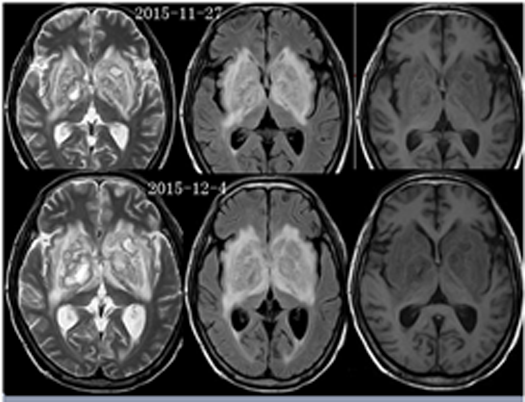

影像资料:

2015-11-27MR:双侧基底节区及双侧大脑脚示较对称片状异常信号, T1WI呈不匀低信号影,T2WI呈不匀高信号影,FLAIR序列呈不匀高信号,累及视交叉、视束及部分丘脑。2015-12-04复查:双侧基底节区及双侧大脑脚病灶范围较前稍增大。2015-12-07增强后病变呈多发环形薄壁或片状强化,DWI呈不均匀高信号。右侧基底节区病灶感兴趣区,可见Cho峰、NAA峰及Cr峰,Cho峰未见明显升高,Cho/Cr比值约为0.34,NAA/Cr比值约为0.56,Cho/NAA比值约0.61。综合平扫、增强、DWI、MRS所见,可排除肿瘤性病变,支持感染性病变(真菌或病毒感染可能性大)。